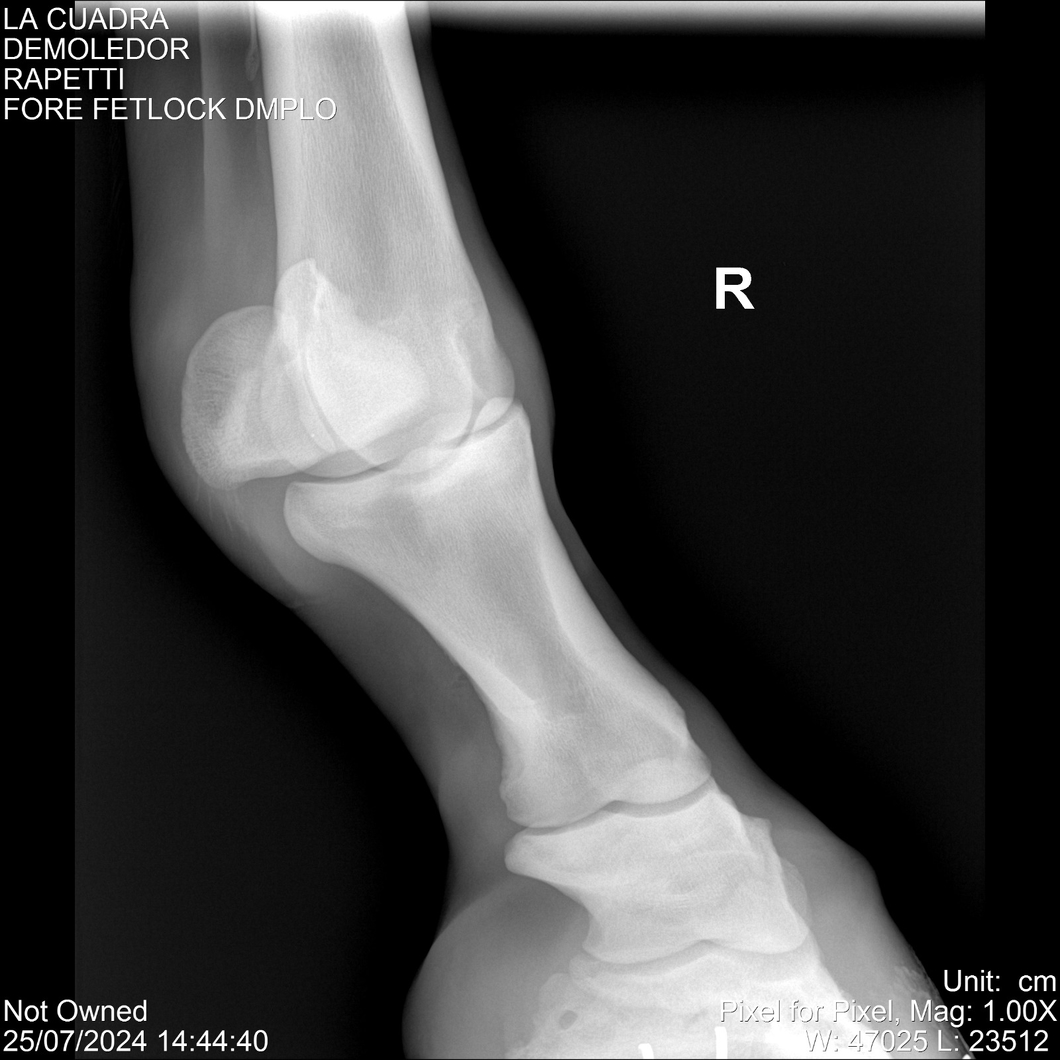

LOTE 14, DEMOLEDOR 🔥 🔥 🔥 Lote Anterior Volver al remate Lote Siguiente Ficha Contacto Montevideo - Ficha del Lote Identificador: #284454 Categoría: Yeguarizos Montevideo - 89 Visualizaciones ClicData Contacto Empresa: Abelenda N. R., Walter Hugo Nombre*: Teléfono* : E-mail* : Mensaje Enviar Registrese gratis Este contenido Exclusivo está disponible sólo para usuarios registrados Ingresar